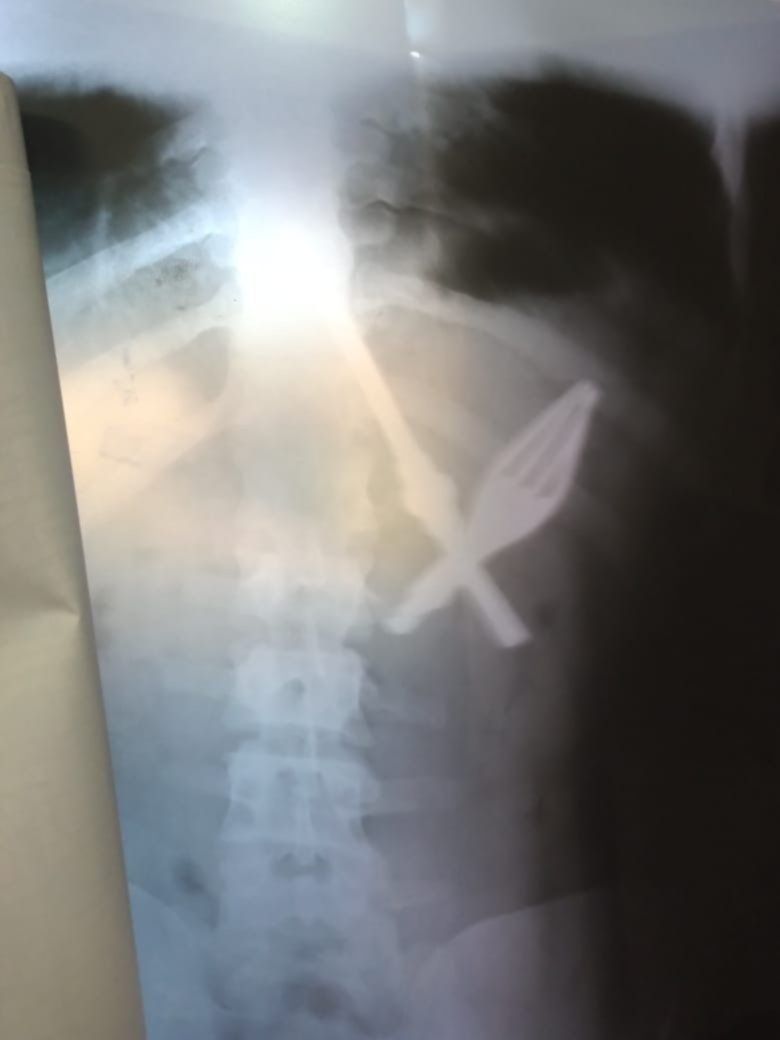

Según informaron fuentes del Servicio Penitenciario Bonaerense (SPB), Crause Lara había sido derivado de la Unidad 35 de Magdalena hacia el hospital San Martín luego de tragarse una bombilla y un tenedor.